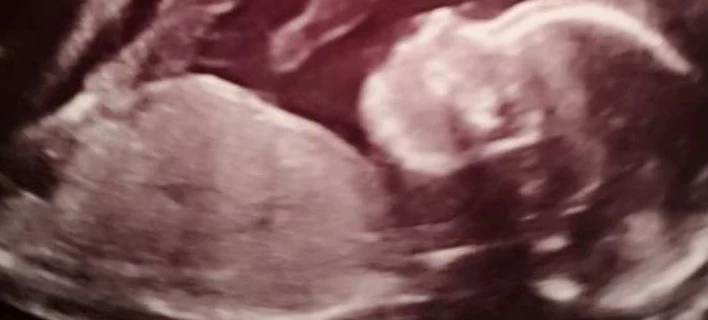

Πρωτοποριακή επέμβαση: Εβγαλαν έμβρυο από τη μήτρα, το εγχείρησαν και το ξανάβαλαν στη θέση του!

Mια πρωτοποριακή επέμβαση έσωσε τη ζωή ενός εμβρύου στη Βρετανία, που το έβγαλαν από τη μήτρα της μητέρας του και μετά την εγχείρηση το ξανάβαλαν στη θέση του! Η Μπέθαν Σίμπσον από το ...